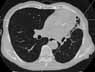

¥ Normal voluntieer

2mmx4, Pitch 3.5, 18 seconds